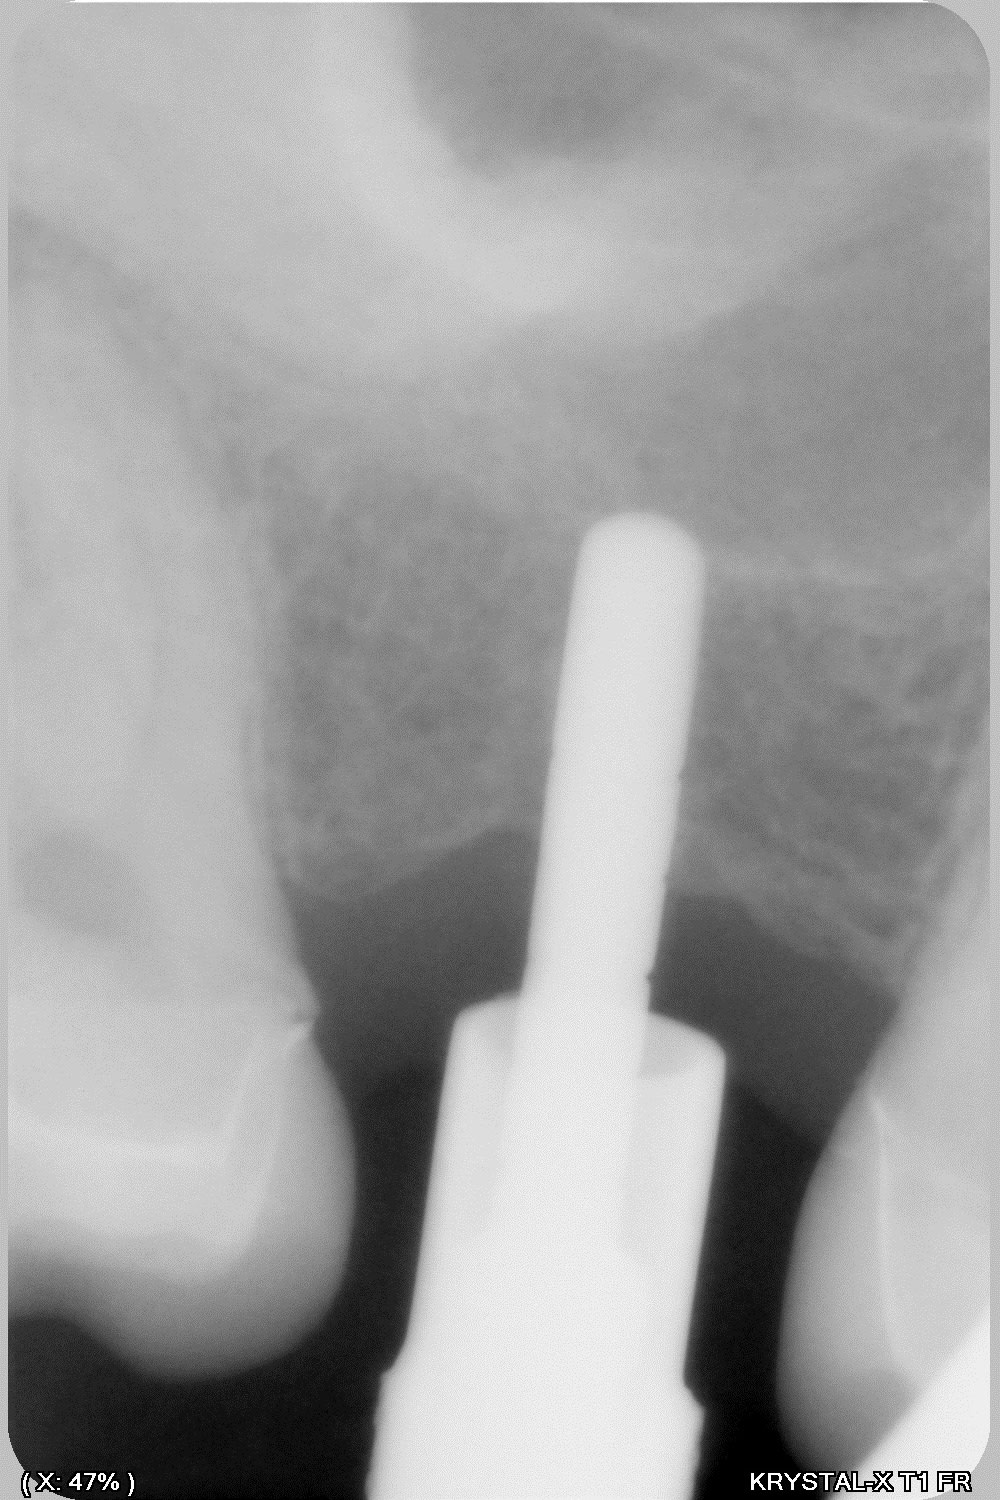

donc tu avais raison Enlaye... le bridge à cassé (sur un carambar quand même:-))

dépose, nettoyage sablage des couronnes récupérable et pose d' implant, uniquement en manuel (os tendre)